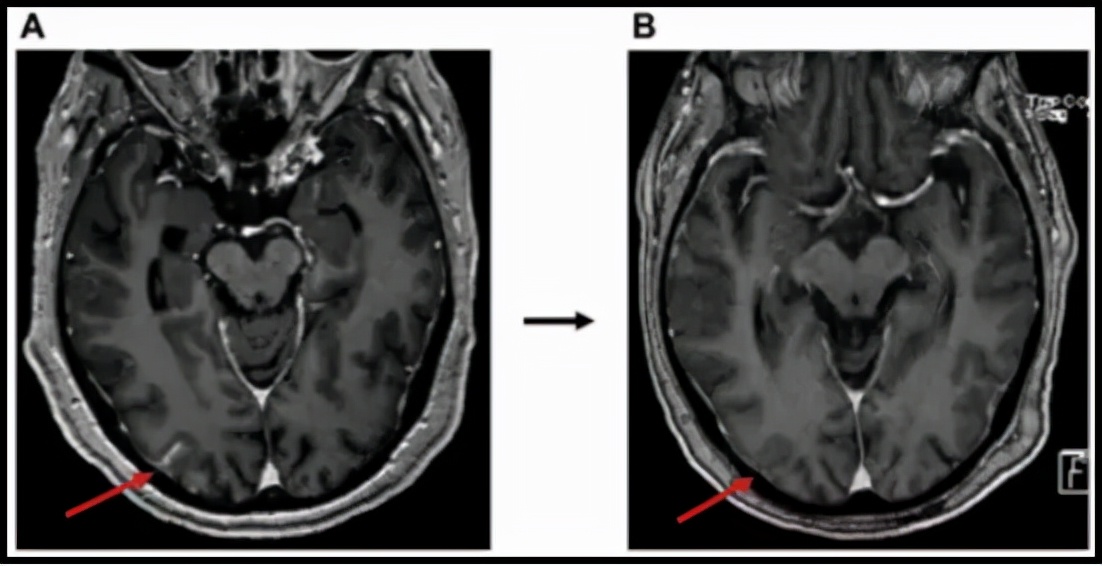

一项发表于《Journal of Clinical Oncology》上的BLOOM 研究,纳入21例EGFR19/21突变的多重耐药(均为二线三线或多线治疗后耐药,且包含EGFR靶向药耐药)软脑膜转移患者,使用奥希替尼加量治疗。

研究结果显示,软脑膜客观缓解率33.33%,疾病控制率达到76.19%。

图示奥希替尼加量前后脑软膜变化,加量后病灶疗效达到部分缓解。